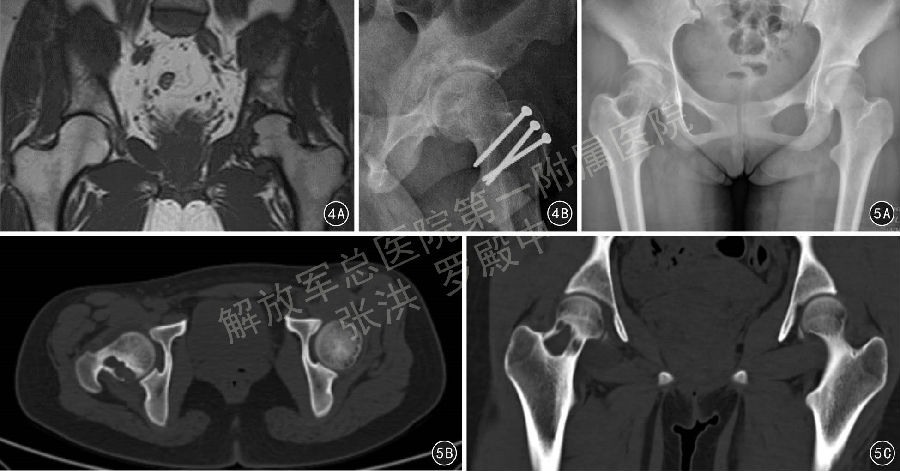

3.6 股骨头颈部严重畸形的处理

对股骨头颈部严重畸形,如股骨头骨骺滑脱、大头畸形等病变,在深入研究股骨头血液供应的临床解剖基础上,Ganz 等在SHD的基础上进一步推出了股骨颈软组织瓣延长技术(图6)。为处理股骨头复杂情况,研究者又开展了股骨头缩小成型术(图7)、股骨颈相对延长术(图7)、股骨头骨骺滑脱复位术(图8)等技术。股骨颈软组织瓣延长技术的手术操作要点是:在SHD 基础上,对大转子后侧突出部分的骨质进行骨膜内剥离、摘除,将股骨颈骨膜连同大转子后方的软组织瓣一同充分游离和松解,避免在对股骨头进行操作时MFCA 过度牵拉造成股骨头缺血。然后在矢状面对股骨头缩小截骨成形、在股骨头颈交界处进行股骨头的内翻/ 外翻截骨以及对严重股骨头骨骺滑脱进行复位,避免继发撞击征和髋骨关节炎形成。

图6 股骨颈软组织瓣延长示意图,6A 仔细切除股骨大转子后缘,进行软组织松解仔细切除股骨大转子后缘,进行软组织松解(红色线条示意旋股内动脉深支于股骨颈骨膜下分数支进入股骨头,股骨颈前外侧虚线为股骨颈骨膜切开线),6B 在保护股骨颈和大转子后侧骨膜的情况下,可以将股骨颈骨膜完全行骨膜下剥离,而不影响股骨头血运

图7 患者女,16岁,左侧扁平髋合并大头畸形,经髋关节外科脱位手术入路行股骨头缩小成形、股骨颈相对延长、髋臼周围截骨手术 7A 术前X线片,7B 术前螺旋CT 3D 重建检查显示头臼明显不匹配,7C 术后1年X线片显示股骨头、大转子截骨处骨愈合良好